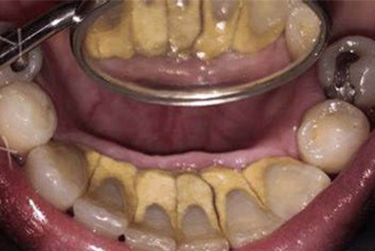

A teeth cleaning is a procedure that removes plaque, food deposits, and stains on teeth. Plaque and tartar can build up on your teeth, causing gum inflammation and degrading gum health. Teeth cleaning can be superficial and deep depending on the condition of gums. Regular teeth cleaning prevents most dental problems.

Teeth cleaning removes plaque and tartar from your teeth, reducing gum inflammation and improving gum health.

The hygienist or dentist uses vibrating tips to remove plaque or tartar on teeth. Cleaning can be completed in one to three sessions based on the severity of gum infection with an interval of 4-5 days.